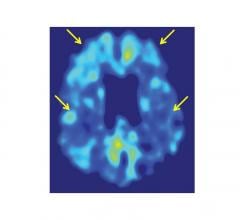

Positron emission tomography (PET) is a nuclear imaging technology (also referred to as molecular imaging) that enables visualization of metabolic processes in the body. The basics of PET imaging is that the technique detects pairs of gamma rays emitted indirectly by a positron-emitting radionuclide (also called radiopharmaceuticals, radionuclides or radiotracer). The tracer is injected into a vein on a biologically active molecule, usually a sugar that is used for cellular energy. PET systems have sensitive detector panels to capture gamma ray emissions from inside the body and use software to plot to triangulate the source of the emissions, creating 3-D computed tomography images of the tracer concentrations within the body.